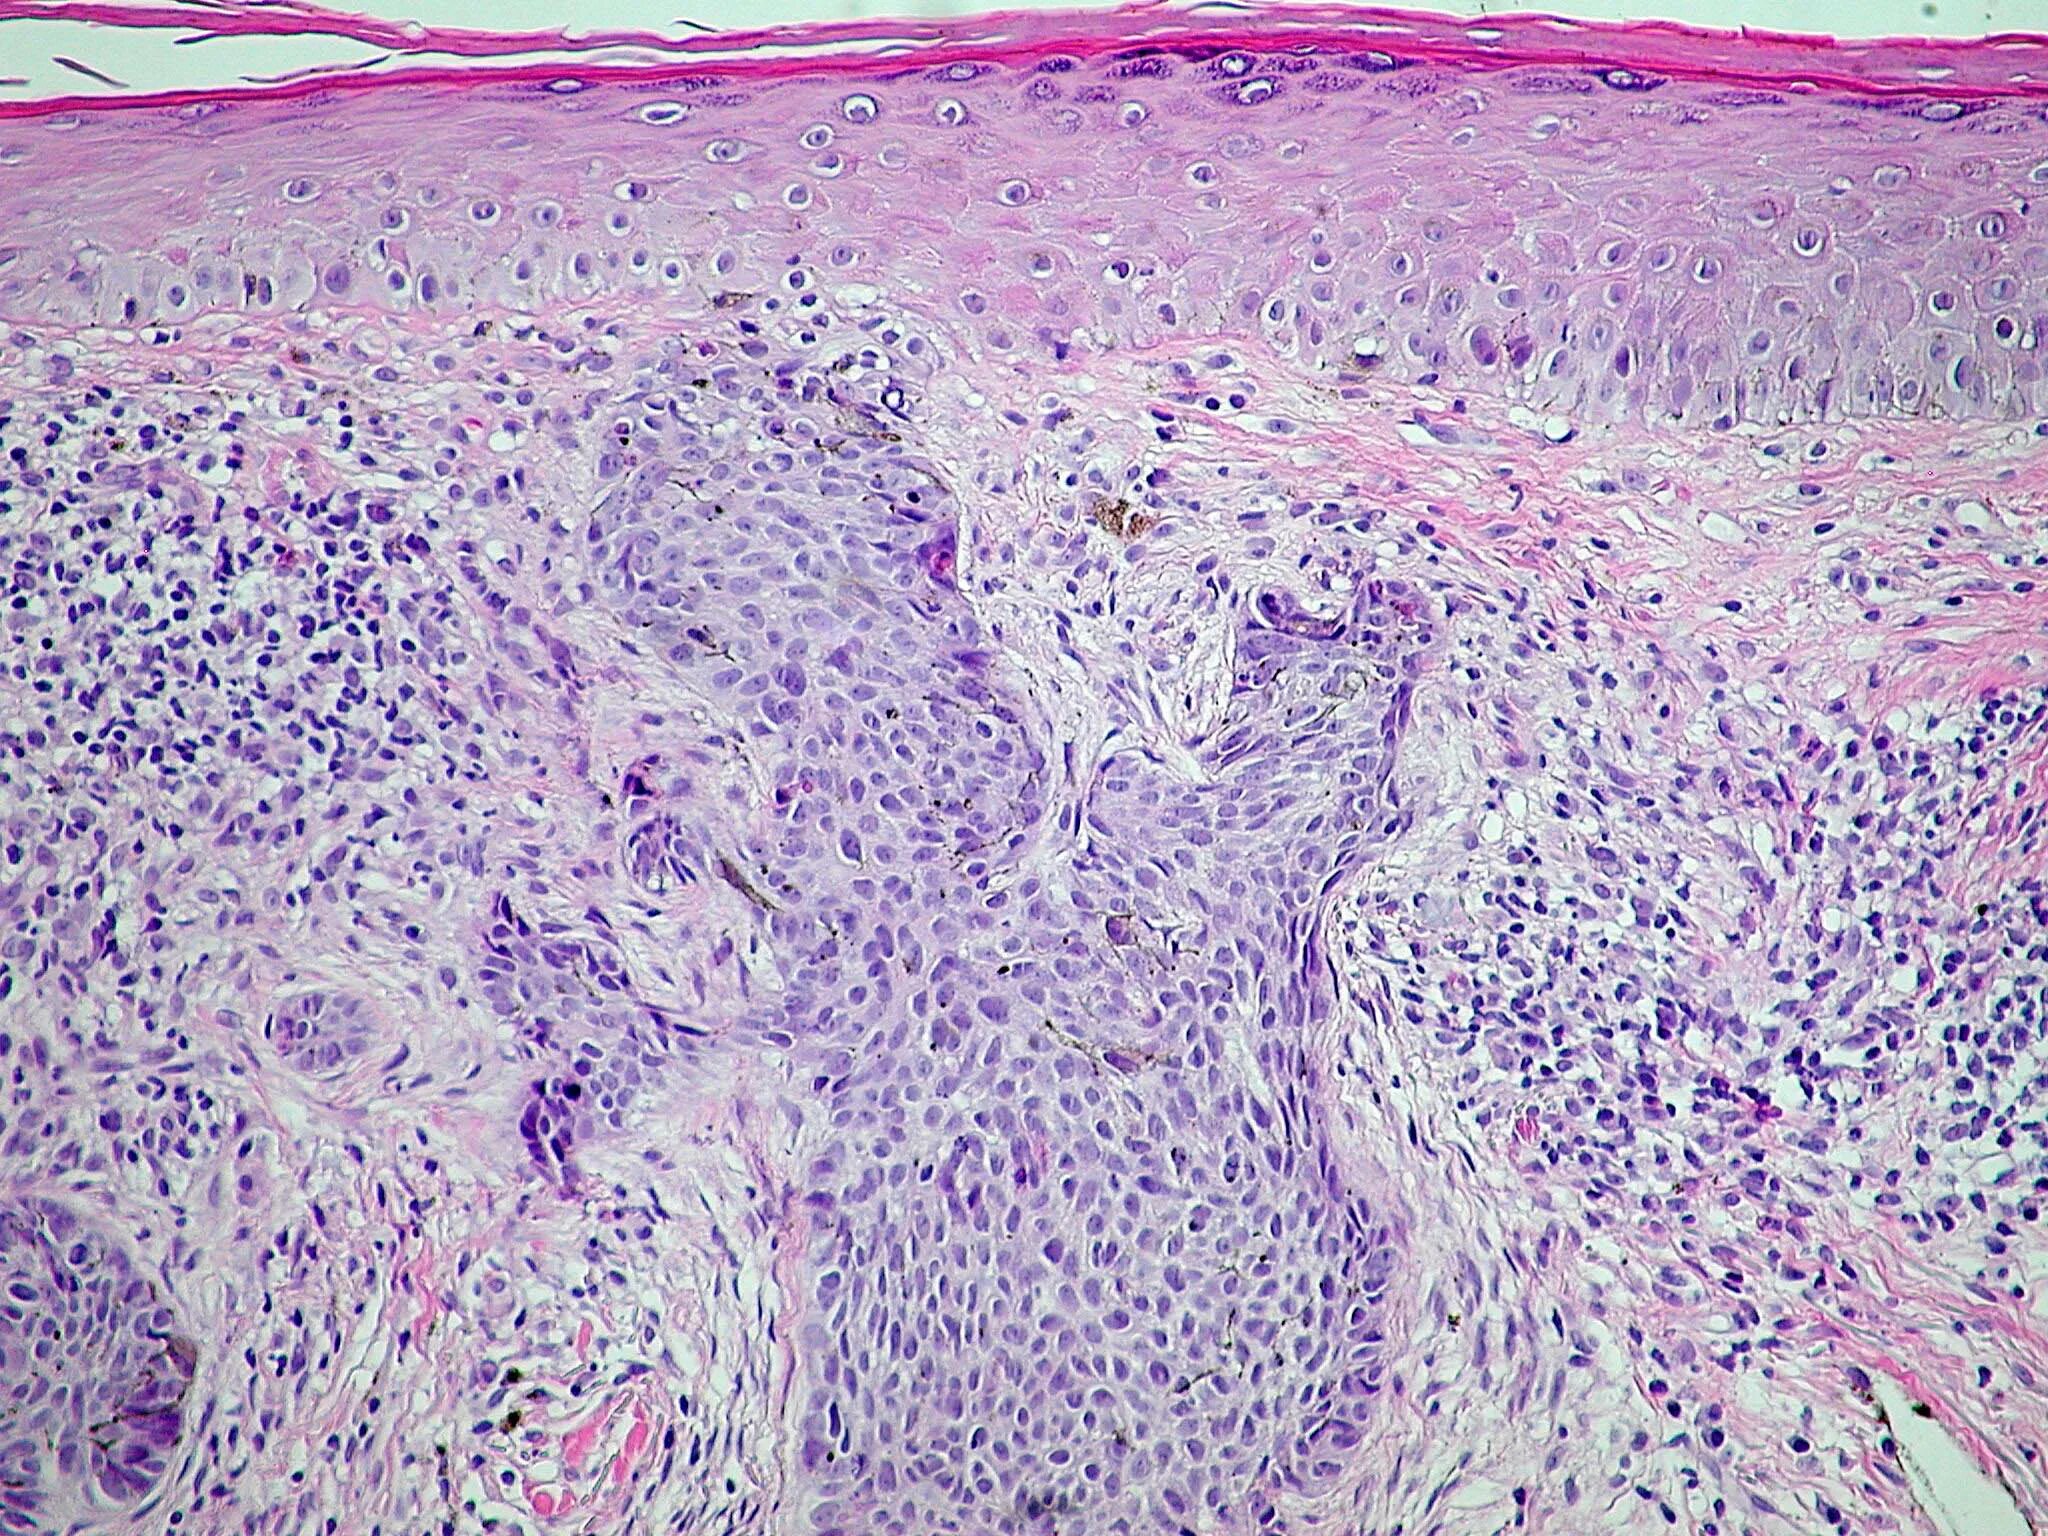

Гистология базалиома